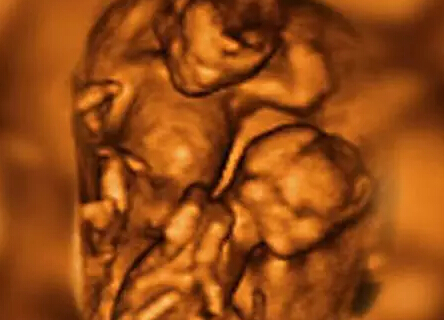

拥挤在子宫里的多胞胎

4-D扫描图显示了双胞胎在子宫中活动的情况。胎儿为了争夺生存空间和养料而彼此推挤。